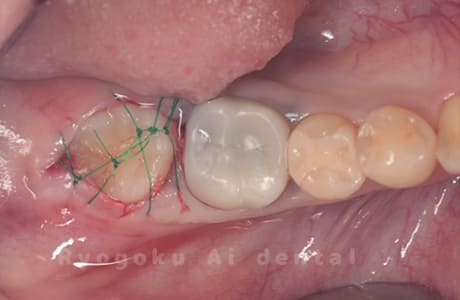

Case27

-

重度カリエス

歯牙移植咬合面術前 -

移植する親知らず

歯牙移植術直後咬合面

歯牙移植術後咬合面

歯牙移植術前側面

歯牙移植術中側面

歯牙移植術後側面

- 原因

- 重度カリエス

- 治療内容

- 自家歯牙移植、部分矯正

- 治療費用

- 220,000円(移植費用)

110,000円(部分矯正費用)

虫歯が大きく、保存不可能となった歯を上の親知らずと交換する自家歯牙移植を行いました。移植歯が小ぶりであったため、部分矯正を行い問題なく噛み合い、経過良好です。